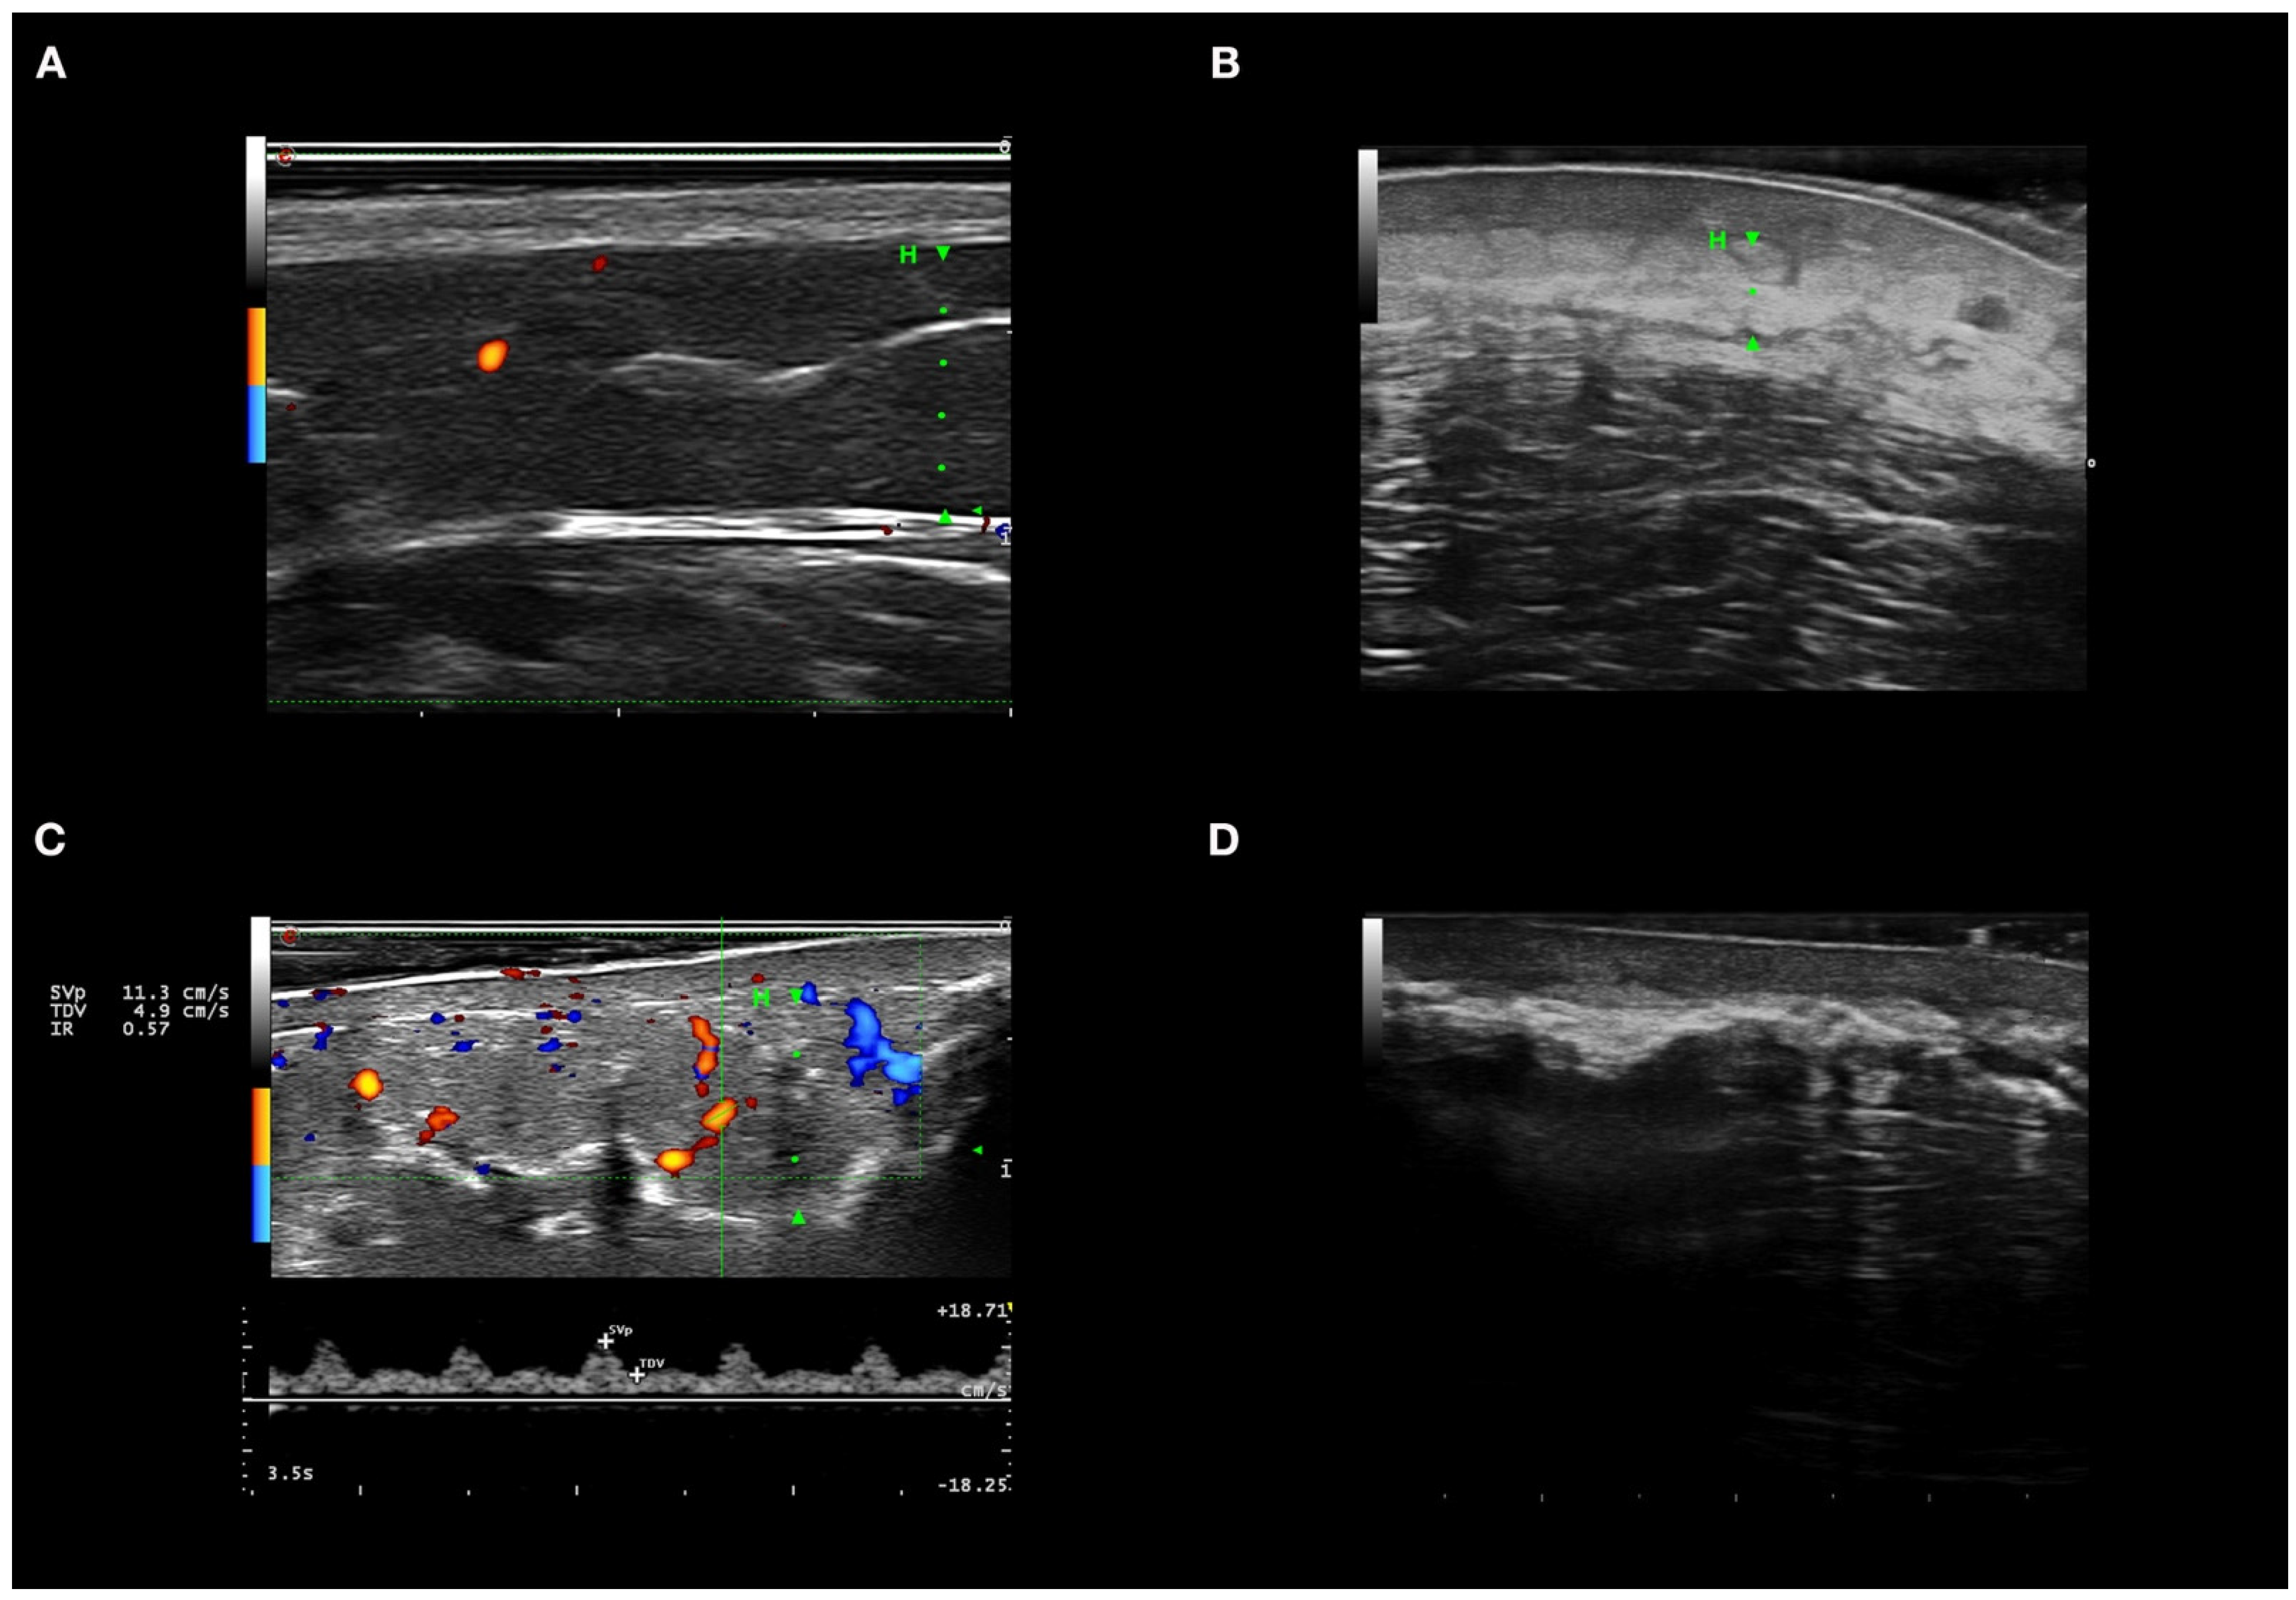

3.5. Ultrasound Features of Inflammation